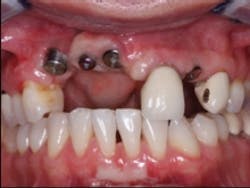

FIG. 1 — Referred patient upon entry into our prosthodontic practice.

I will use a recent case, which has the conditions you described, to show my suggestions to you. A competent surgical specialist who had very few optimum clinical conditions present when placing the implants sent me this case (Fig. 1).